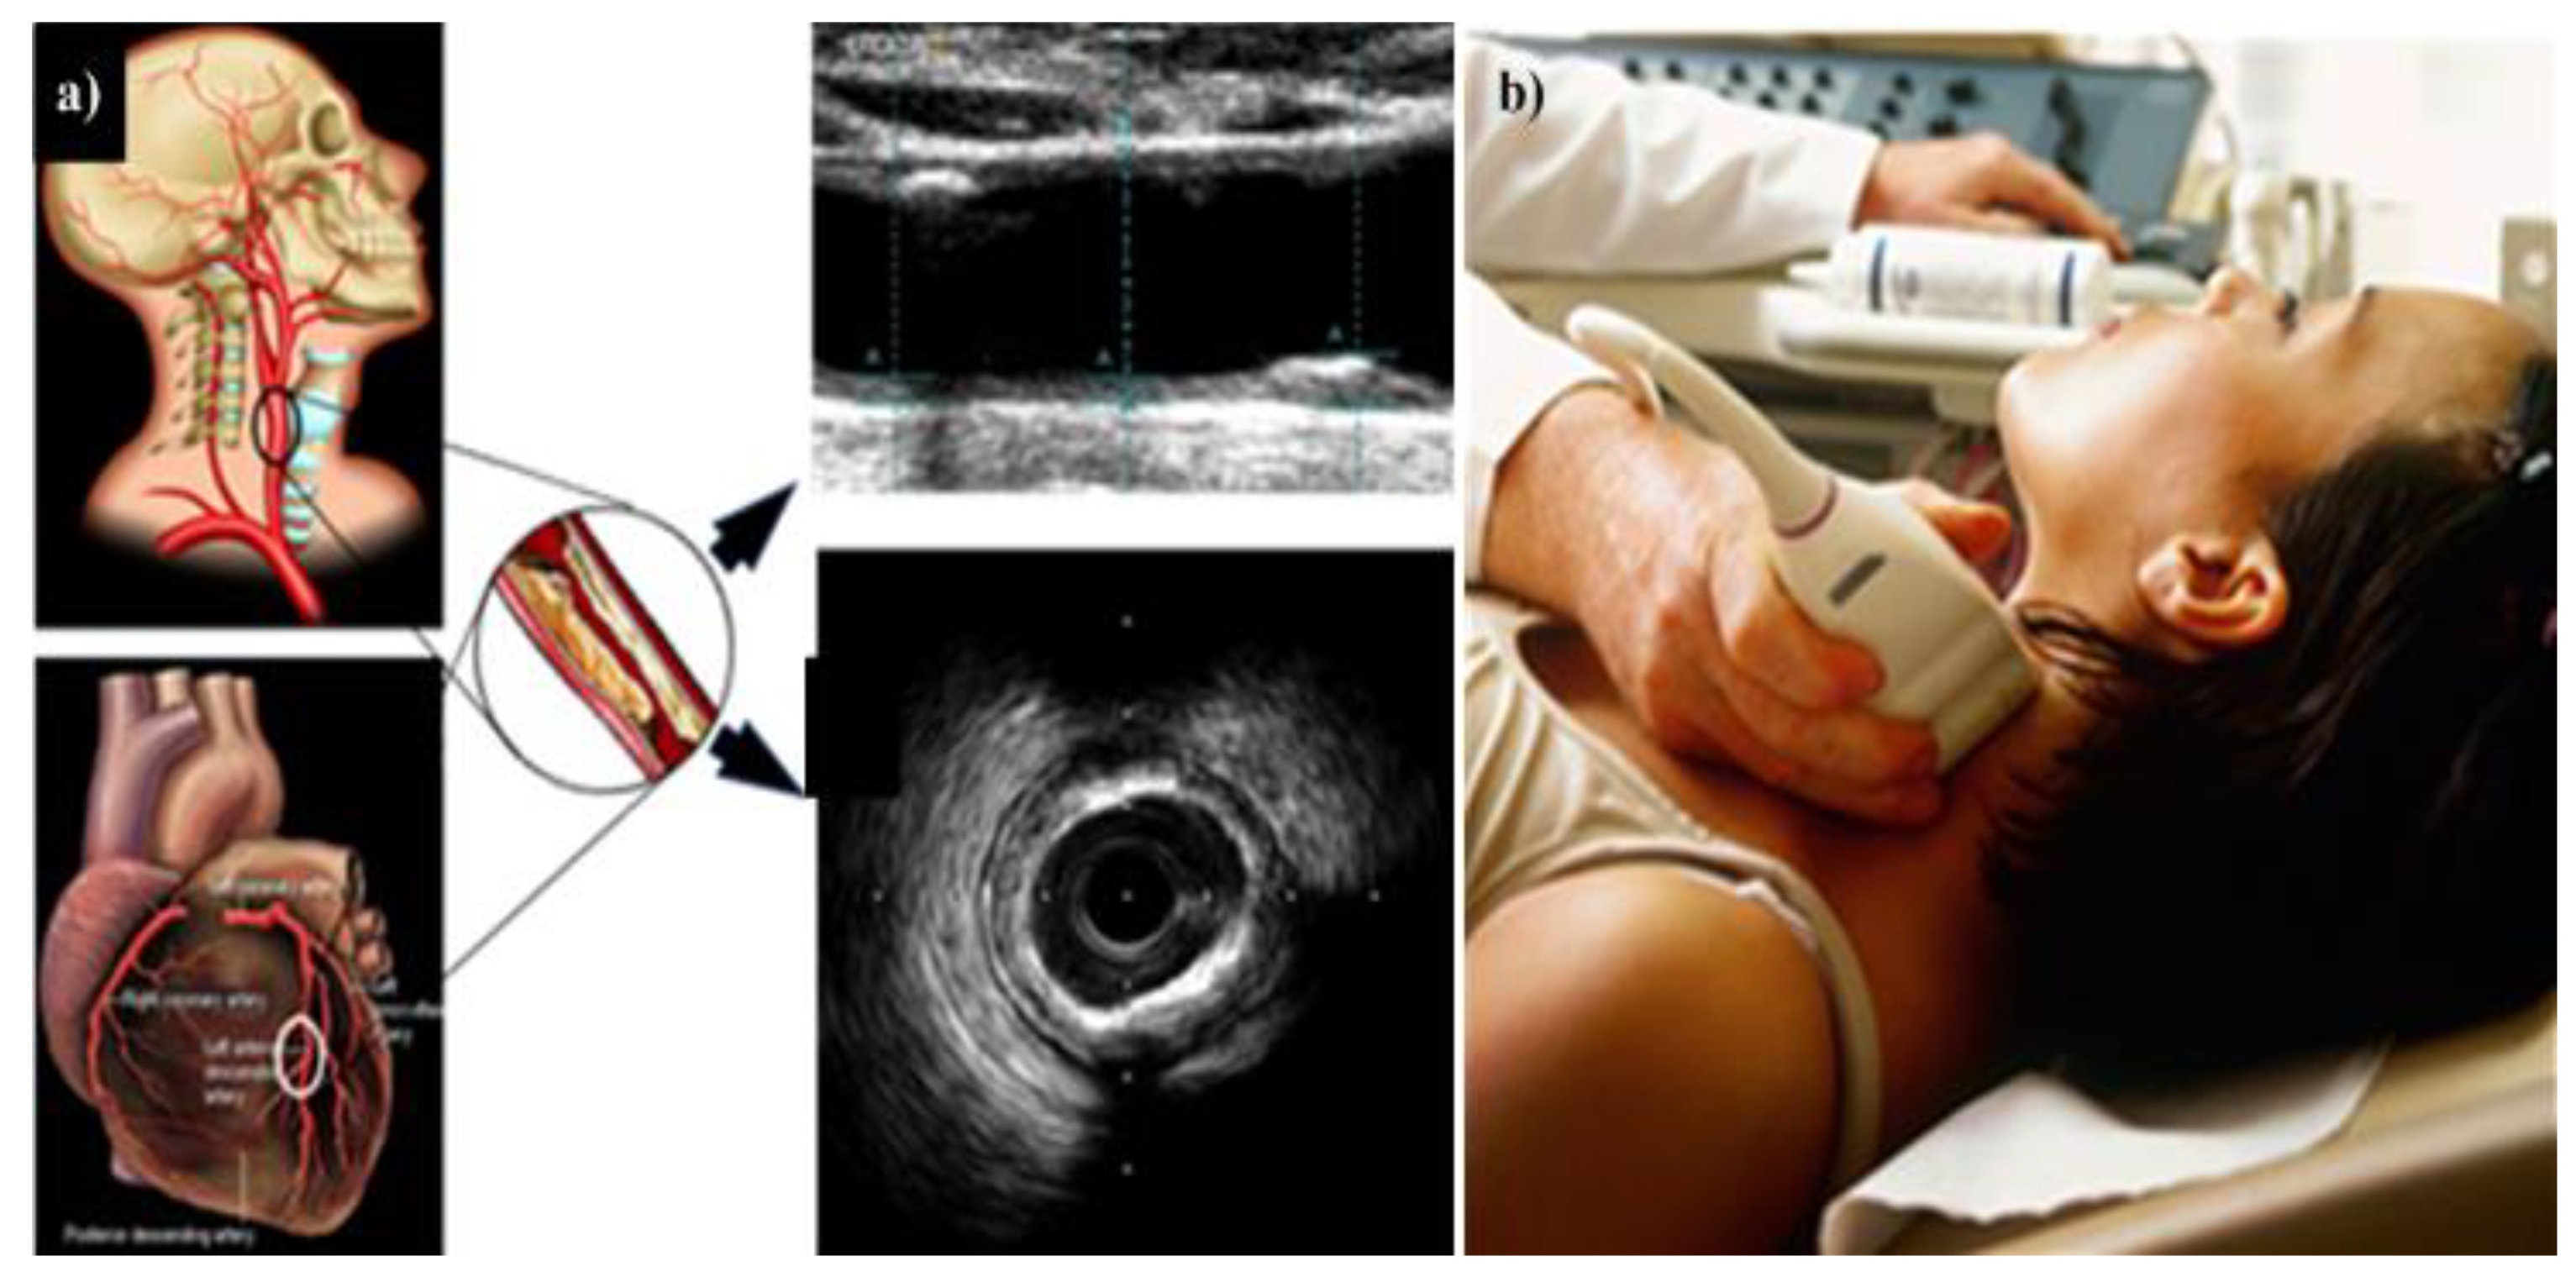

- Boi, A.; Jamthikar, A.D.; Saba, L.; Gupta, D.; Sharma, A.; Loi, B.; Laird, J.R.; Khanna, N.N.; Suri, J.S. A Survey on Coronary Atherosclerotic Plaque Tissue Characterization in Intravascular Optical Coherence Tomography. Curr. Atheroscler. Rep. 2018, 20, 33. [Google Scholar] [CrossRef]

- Laine, A.; Sanches, J.M.; Suri, J.S. Ultrasound Imaging: Advances and Applications; Springer: Berlin, Germany, 2012. [Google Scholar]

- Suri, J.S. Advances in Diagnostic and Therapeutic Ultrasound Imaging; Artech House: London, UK, 2008. [Google Scholar]

- Beach, K.W. Principles of Ultrasonic Imaging and Instrumentation. In Ultrasound and Carotid Bifurcation Atherosclerosis; Nicolaides, A., Beach, K.W., Kyriacou, E., Pattichis, C.S., Eds.; Springer: London, UK, 2012; pp. 67–96. [Google Scholar]